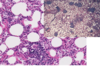

This is the stomach of a horse. What lesion is shown here?

equine gastric ulceration